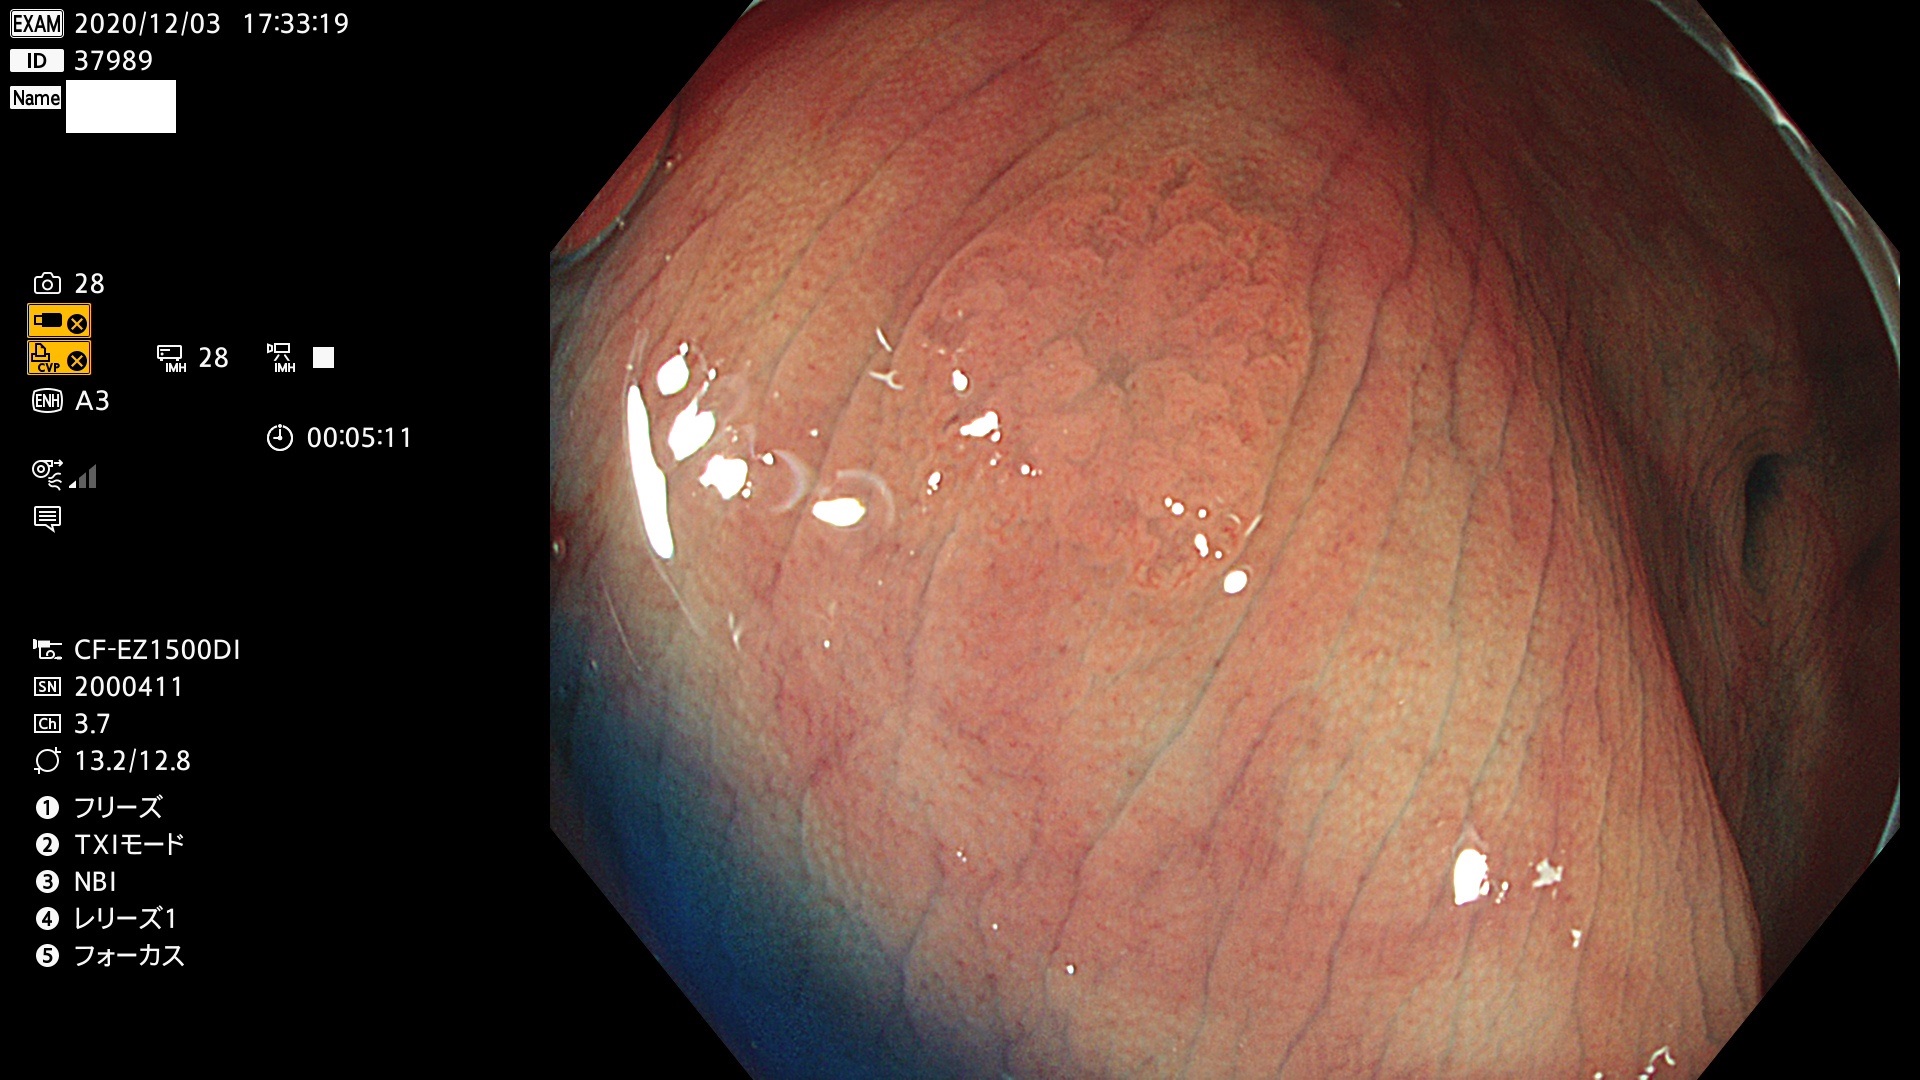

発見困難で危険性の高い平坦型病変(上記100名より抽出)

37900 37902 37903 37904 37905 37906 37907 37909 37910 37911 37912 37913 37914 37915 37916 37917 37919 37921 37922 37923 37926 37928 37929 37930 37931 37933 37934 37935 37936 37937 37938(SSAPのみ) 37939 37940 37941 37942 37943 37946 37947 37948 37949 37951 37952 37953(SSAPのみ) 37955 37956 37957(SSAPのみ) 37958(SSAPのみ) 37960 37962 37963 37964 37966 37967 37968 37971 37972 37973 37975 37976 37977 37979 37982 37983 37984 37985 37986 37987 37988 37989 37990 37991 37992 37993 37994 37995 37996 37998 37999